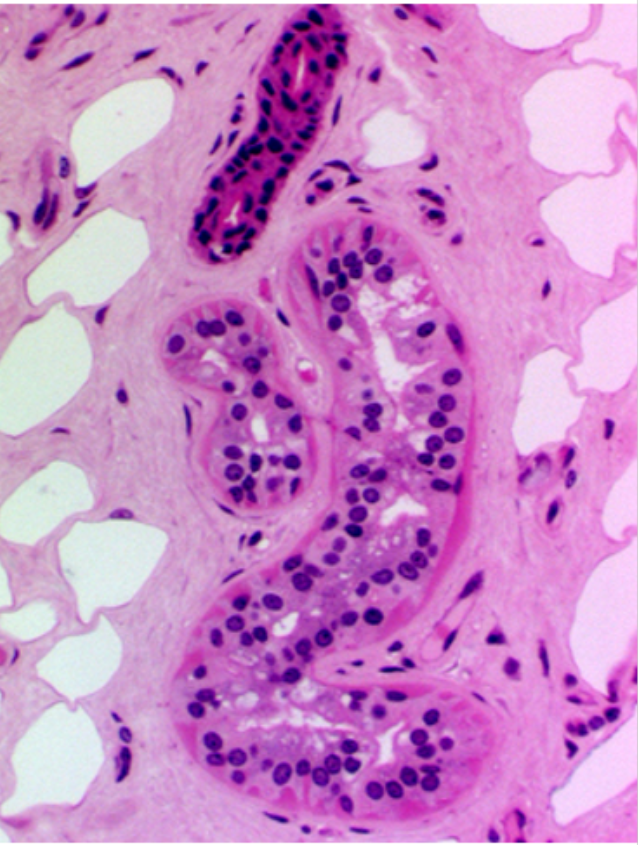

the red is

sweat gland duct

the blue is

glandular part of sweat duct